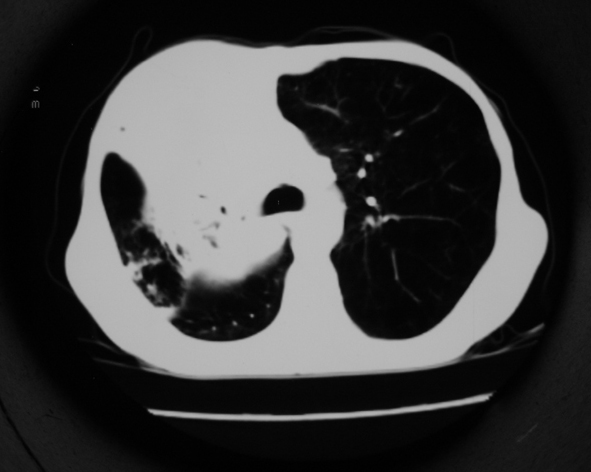

男53岁,咳嗽气短,以往身体健康.

右肺上叶多发多形态空洞及增殖灶,可见团块钙化,胸膜肥厚、粘连,考虑继发型肺结核可能性大

1.右肺上叶干酪性肺炎,2。肺气肿,肺大泡

支持右上肺继发性肺结核并干酪性肺炎,右肺大泡,左肺代偿性气肿。